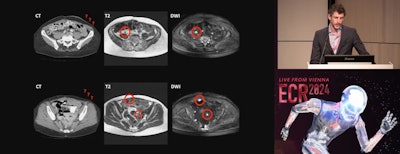

Research from a leading Dutch center presented at ECR 2024 suggests that diffusion-weighted MRI (DW-MRI) has value in ovarian cancer treatment planning.

In his talk, Dr. Max Lahaye, PhD, a postdoctoral fellow from the Netherlands Cancer Institute in Amsterdam, discussed his team's findings that showed that DW-MRI can perform a complete primary and interval debulking with high accuracy. "We as radiologists have a problem in depicting disease on CT, peritoneal disease. We have a sensitivity of 11% for lesions smaller than 5 mm. That's really low. While on MRI, especially on diffusion-weighted images, these lesions light up like a lightbulb," he told ECR attendees.

Max Lahaye, MD, of the Netherlands Cancer Institute in Amsterdam presents findings on the clinical impact of dedicated MR staging of ovarian cancer patients during ECR 2024.